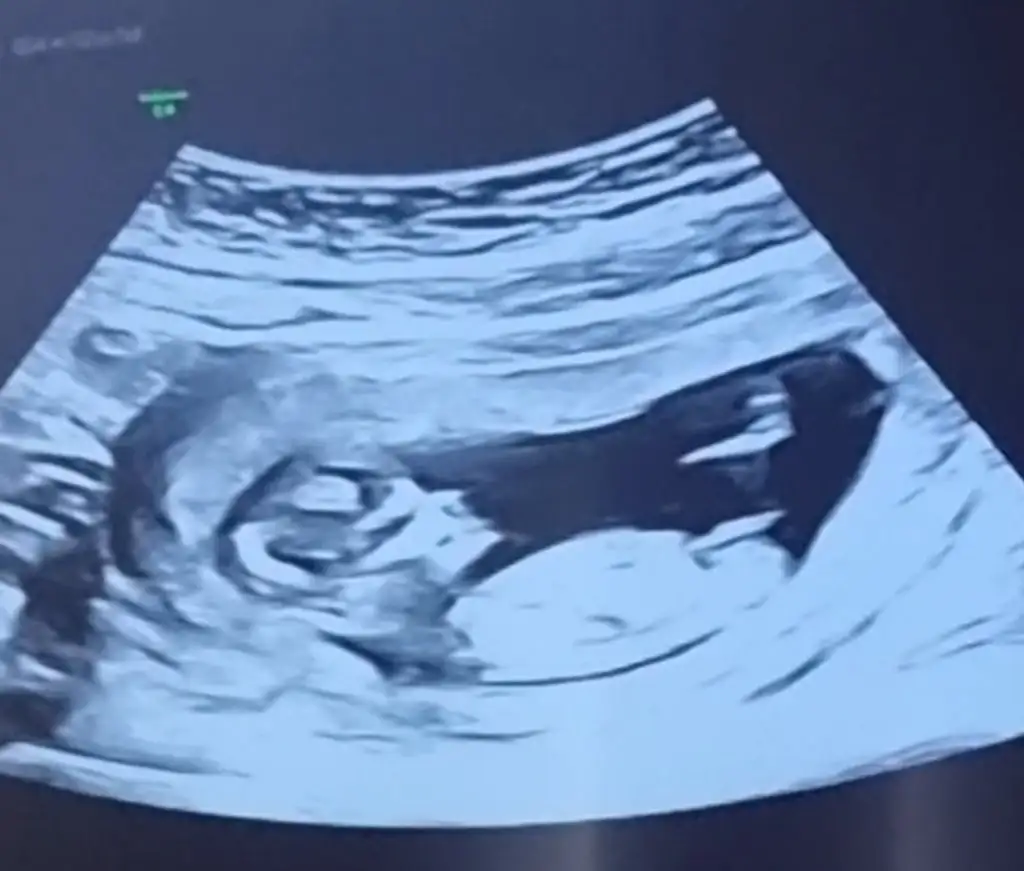

Bu gercekten daha doluOmu doluo dolu ise bu nedir 13 haftaEki Görüntüle 2826253

Erkek görünüyorRica etsem ben de bir tahmin alabilir miyim 11+5 ultrasonu :)